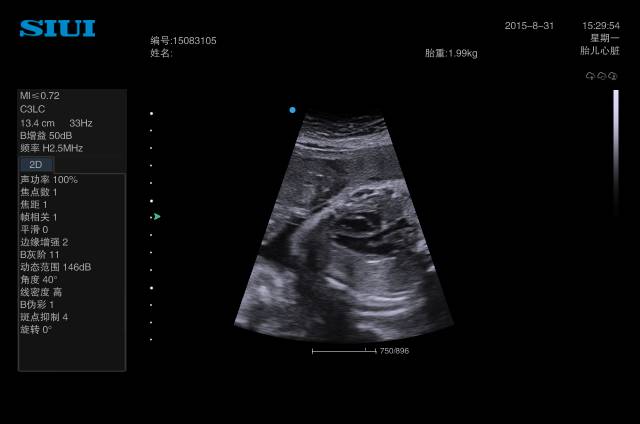

39、晚孕单胎臀位胎儿,内脏结构显示不满意的,可以让孕妇倒过来躺效果会好些,尤其心脏结构。